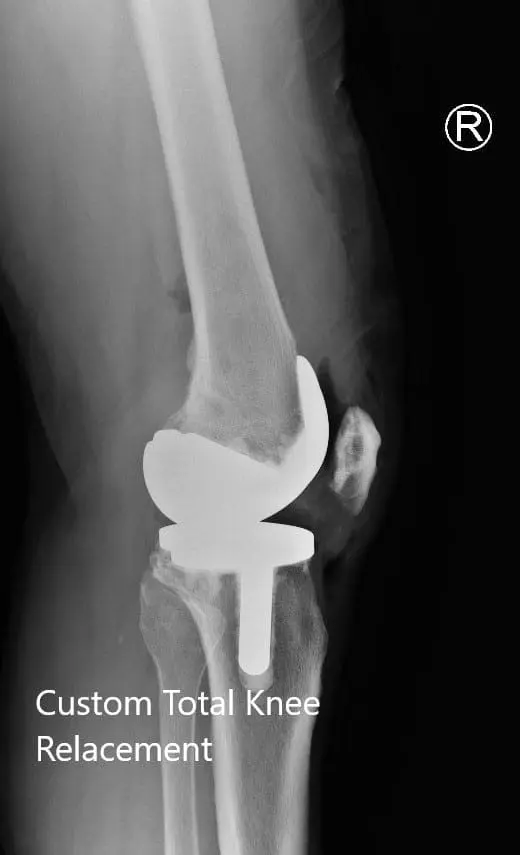

PROCEDURE: Bilateral total knee arthroplasty.

IMPLANTS USED: Custom femoral implant with a tibial tray with 6-mm polyethylene inserts on the right side with 29-mm patellar component. Custom femoral implant with a custom tibial tray with 6-mm polyethylene inserts on the left side with the 32-mm patellar implant.

Postoperative X-ray showing the lateral views of both knees

Postoperative X-ray showing the lateral views of both knees - img 2

Postoperative X-ray showing the lateral views of both knees.